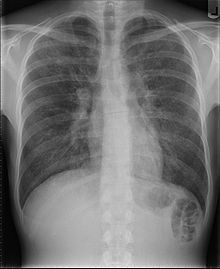

- Candidose von Bronchien, Luftröhre oder Lungen

- Pneumocystis-Pneumonie

- Pneumonien, bakteriell rezidivierend (> zwei innerhalb eines Jahres)

1981 beschrieb Michael S. Gottlieb in der am 5. Juni erschienenen Ausgabe des Morbidity and Mortality Weekly Report, einem wöchentlichen Bulletin der US-Gesundheitsbehörde Centers for Disease Control and Prevention (CDC), eine Häufung einer seltenen Form der Lungenentzündung. Diese durch den Pilz Pneumocystis jirovecii ausgelöste Form befällt nahezu ausschließlich Patienten mit schwerwiegender Immunschwäche, wurde von Gottlieb jedoch bei fünf zuvor gesunden, homosexuellen Männern in Los Angeles festgestellt. Ähnliche Berichte aus anderen US-amerikanischen Städten folgten. Zudem wurden verstärkt auch andere opportunistische Erkrankungen – etwa Kaposi-Sarkome – festgestellt, die überwiegend Patienten mit geschwächtem Immunsystem befallen.